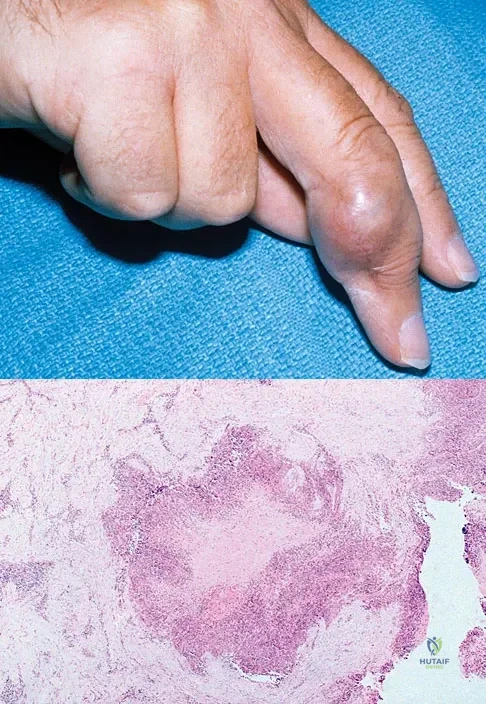

Figure 18a shows the clinical photograph of a 31-year-old man who has a slowly growing nodule on his right middle finger. It is minimally tender, and there is no erythema on examination. A biopsy specimen is shown in Figure 18b. What is the most likely diagnosis?

Explanation